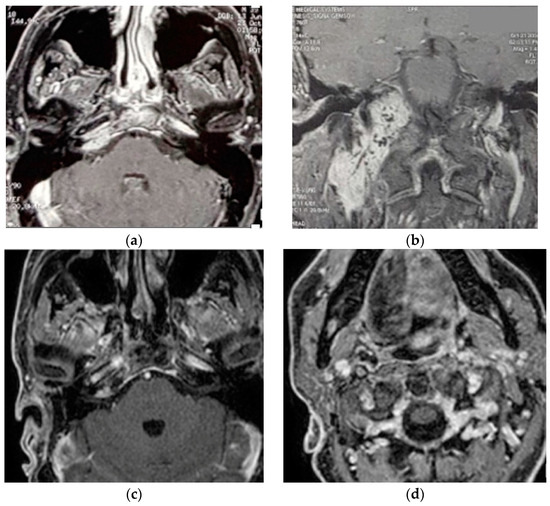

5.1. Case 1: (C4Di2)

5.2. Case 2: (C3Di1 + Stage I VP)

5.3. Case 3: (C4Di2Vi)

5.4. Case 4: (C3Di2 + Stage II Vagal PGL)

5.5. Case 5: (C3Di2Vi)

5.6. Case 6: (C4Di2Vi)